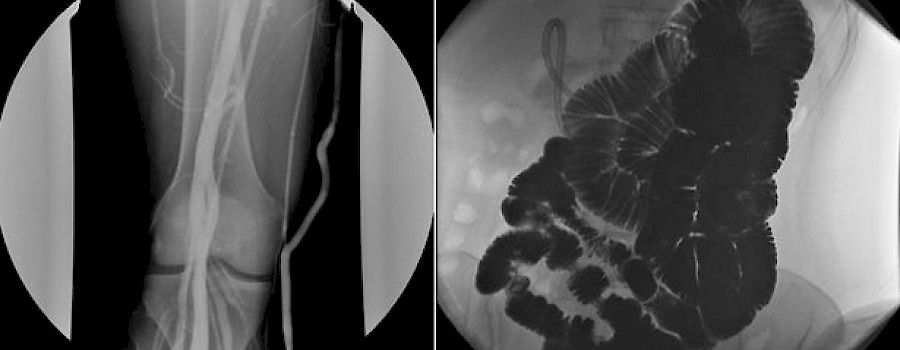

Dürfen Durchleuchtungen an MTA-R delegiert werden?

Darf oder kann ein Radiologe einer(m) MTA-R, MFA oder sonstigem medizinischem Personal eine Durchleuchtungsuntersuchung durchführen lassen?